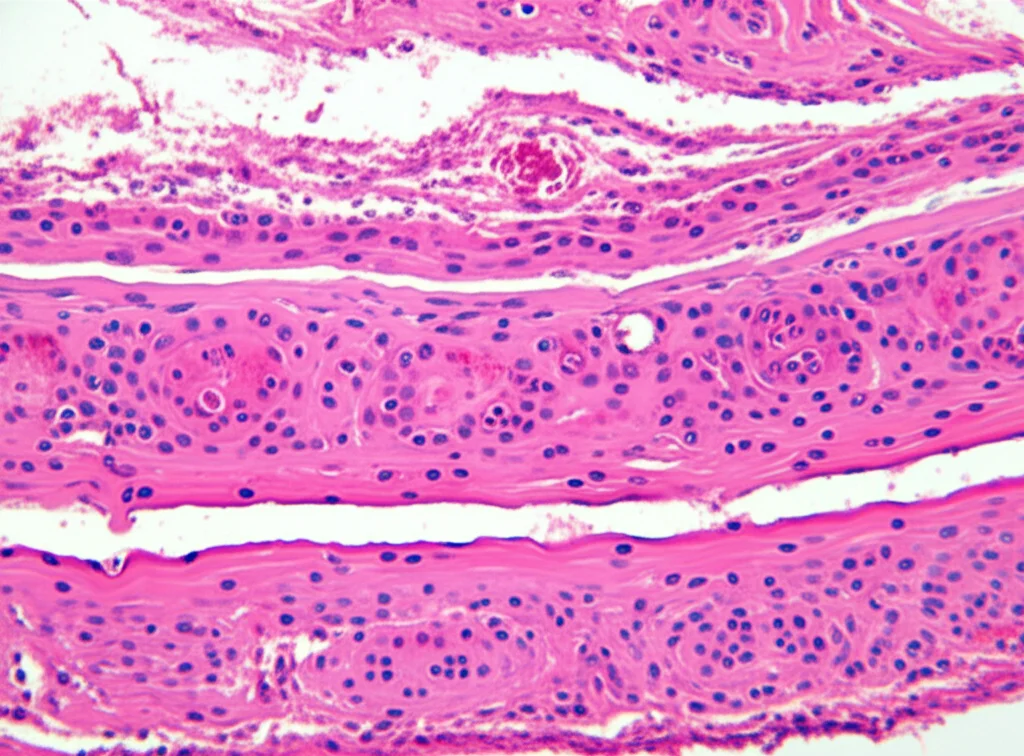

Beh, la preoccupazione esiste, non neghiamolo. Quando si fa una biopsia, si prelevano piccoli campioni di tessuto prostatico. Questo, inevitabilmente, causa una reazione locale: un po’ di infiammazione, magari qualche piccolo ematoma, e nel tempo può portare a fibrosi o aderenze tra l’adenoma (la parte ingrossata della prostata che dobbiamo rimuovere) e la capsula prostatica (l’involucro esterno). Immaginate di dover “scollare” delicatamente questi tessuti durante l’intervento: se ci sono aderenze o tessuto infiammato, l’operazione potrebbe diventare più complessa, più lunga e, potenzialmente, con qualche rischio in più.